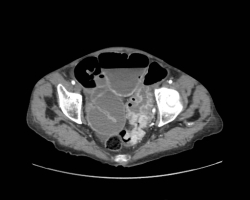

L’arthrose de hanche ou coxarthrose est une maladie fréquente, consistant en une lésion de l’articulation de la hanche, cartilage et os, d’origine mécanique. […]